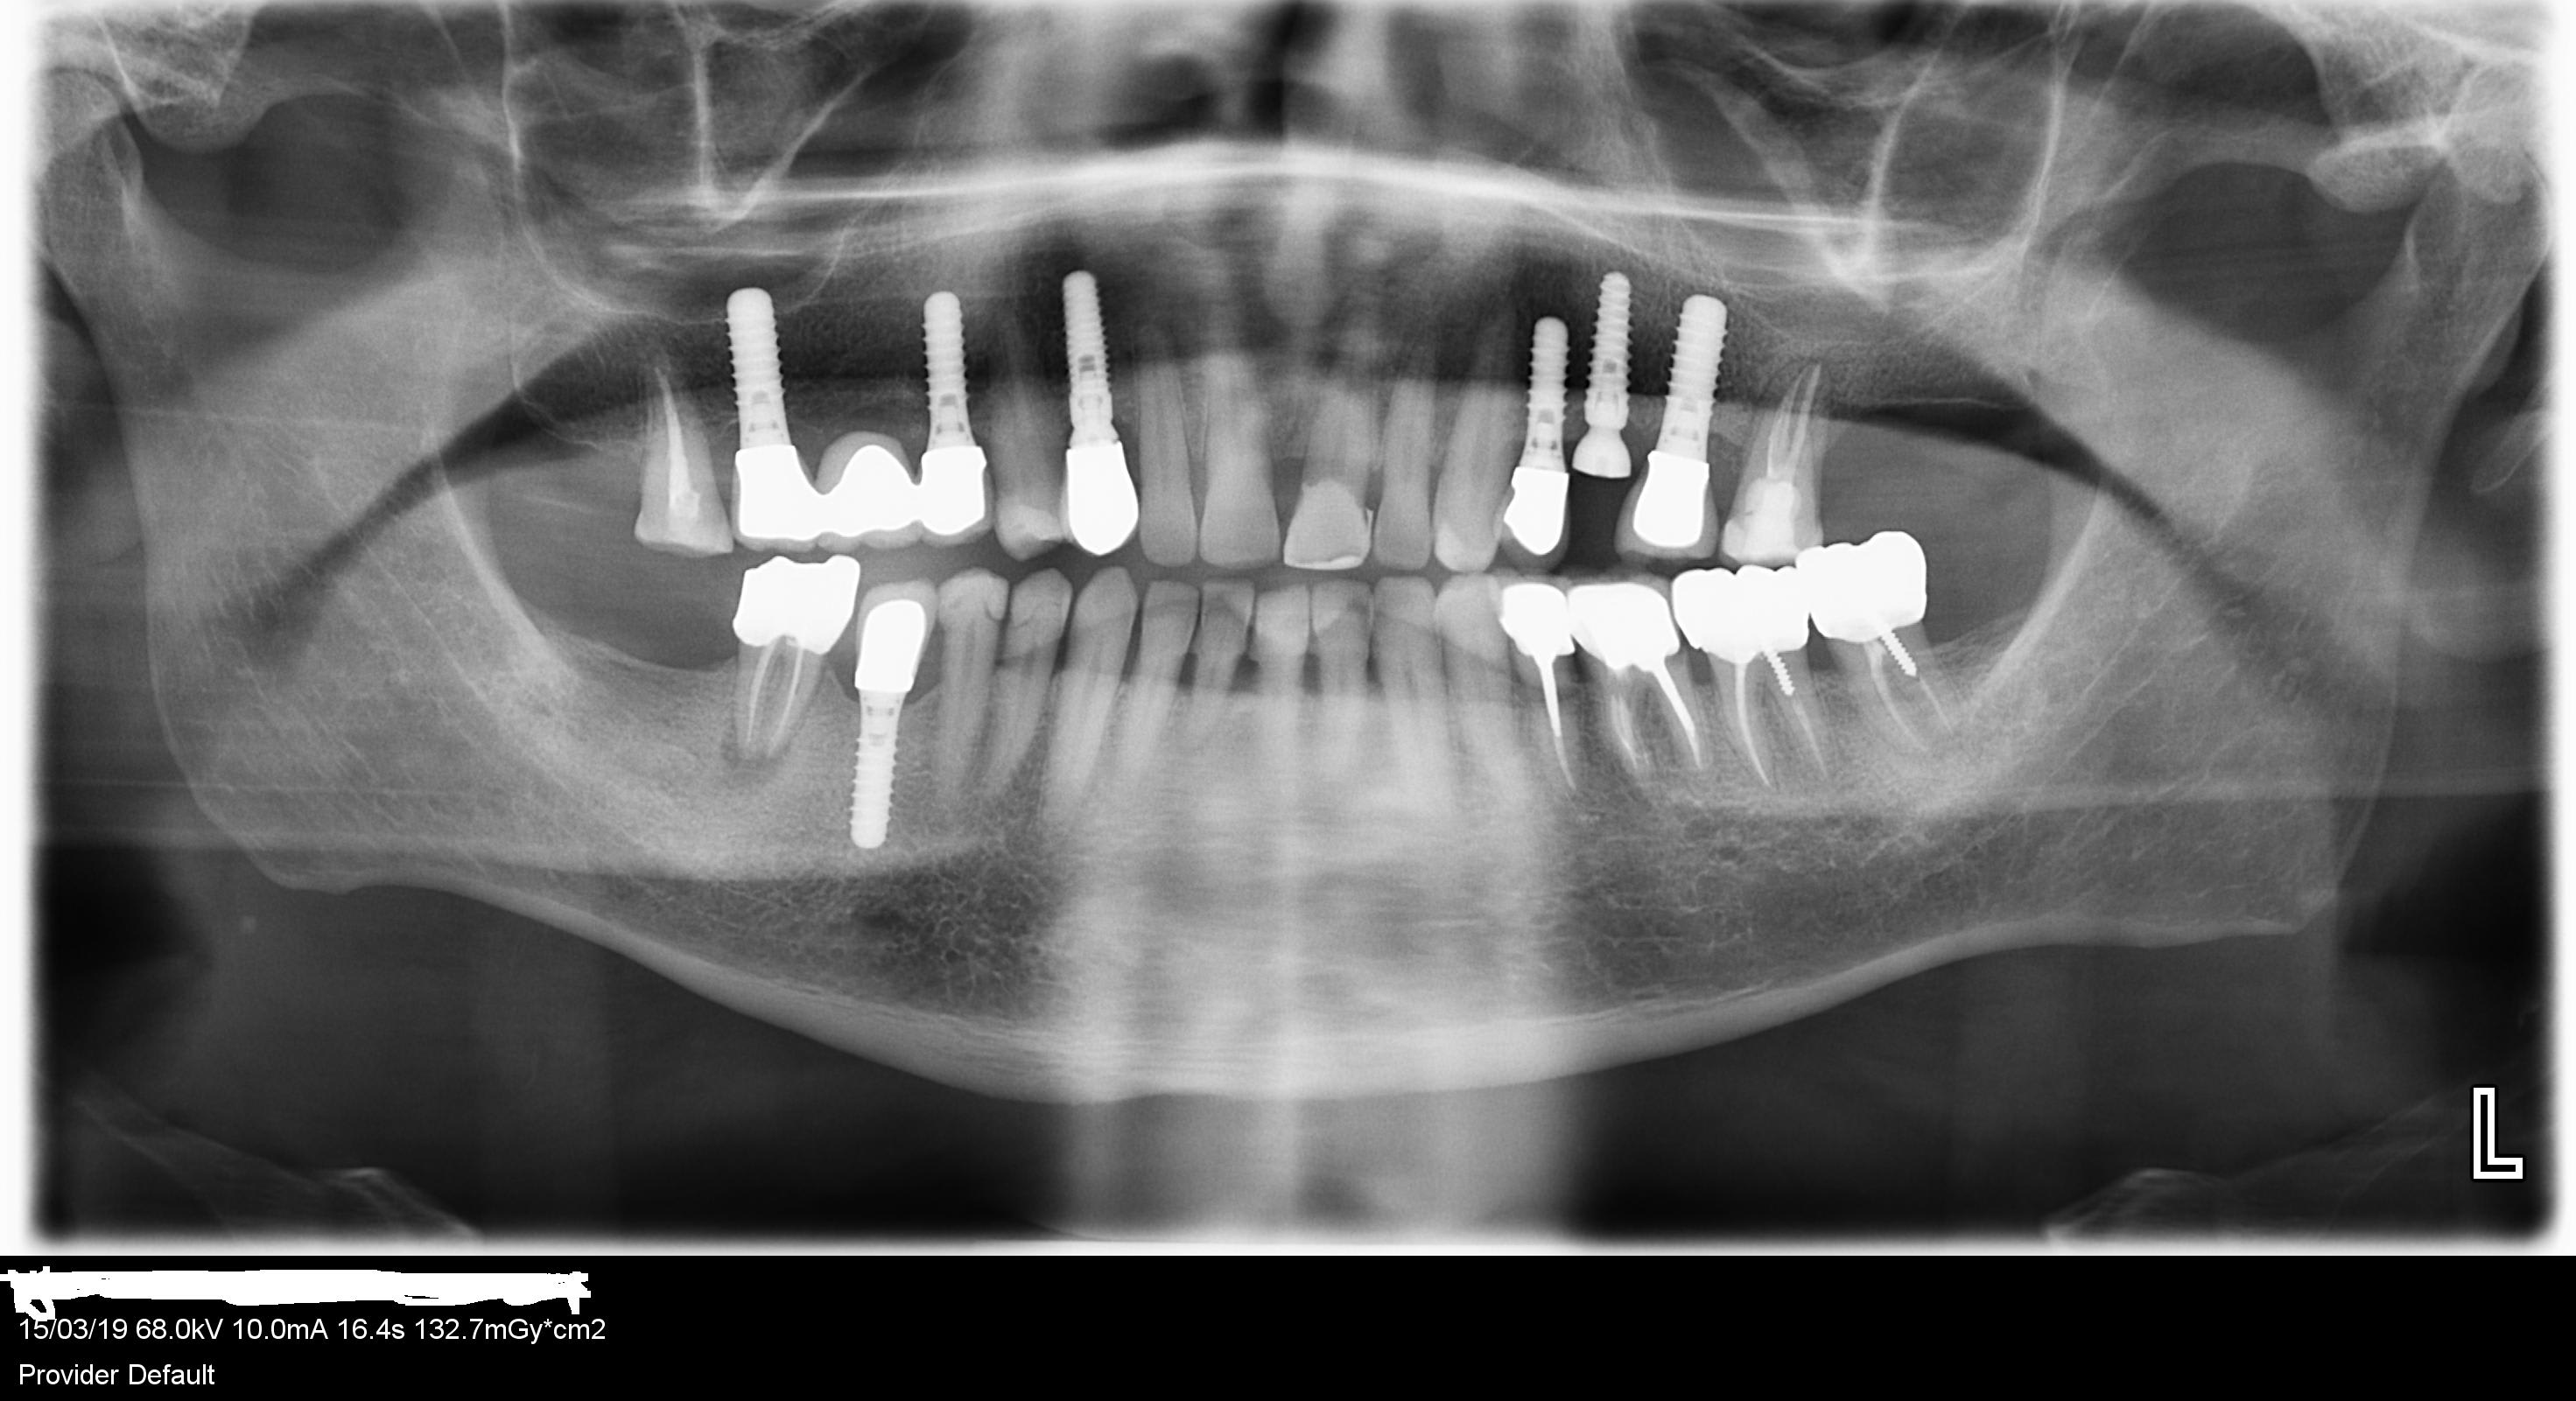

Merci pour m' aider à reconnaitre les implants en 25 et 26 :

25 à faire et 26 à refaire car dévissé , j' ai été obligé de couper la couronne

rétroalvéolaire stp....même si ta pano est bonne çà ne donne pas autant de détails....

sur la 26 c'est certainement du Straumann

sur la 25 par contre j'hésite entre plusieurs marques....(avec une préférence pour un axiom PX....mais bon je suis pas certain...)

Je suis d'accord pour du Strauman standard ou standard plus en 3.3 et en 4.1

Autant pour moi . C'est 24 et 26 Strauman pour la 25 je ne sais pas ressemble a un blt mais pas sûr du tout

Bonjour, je reviens sur le cas de l'implant en 25, voici les retro alveolaires